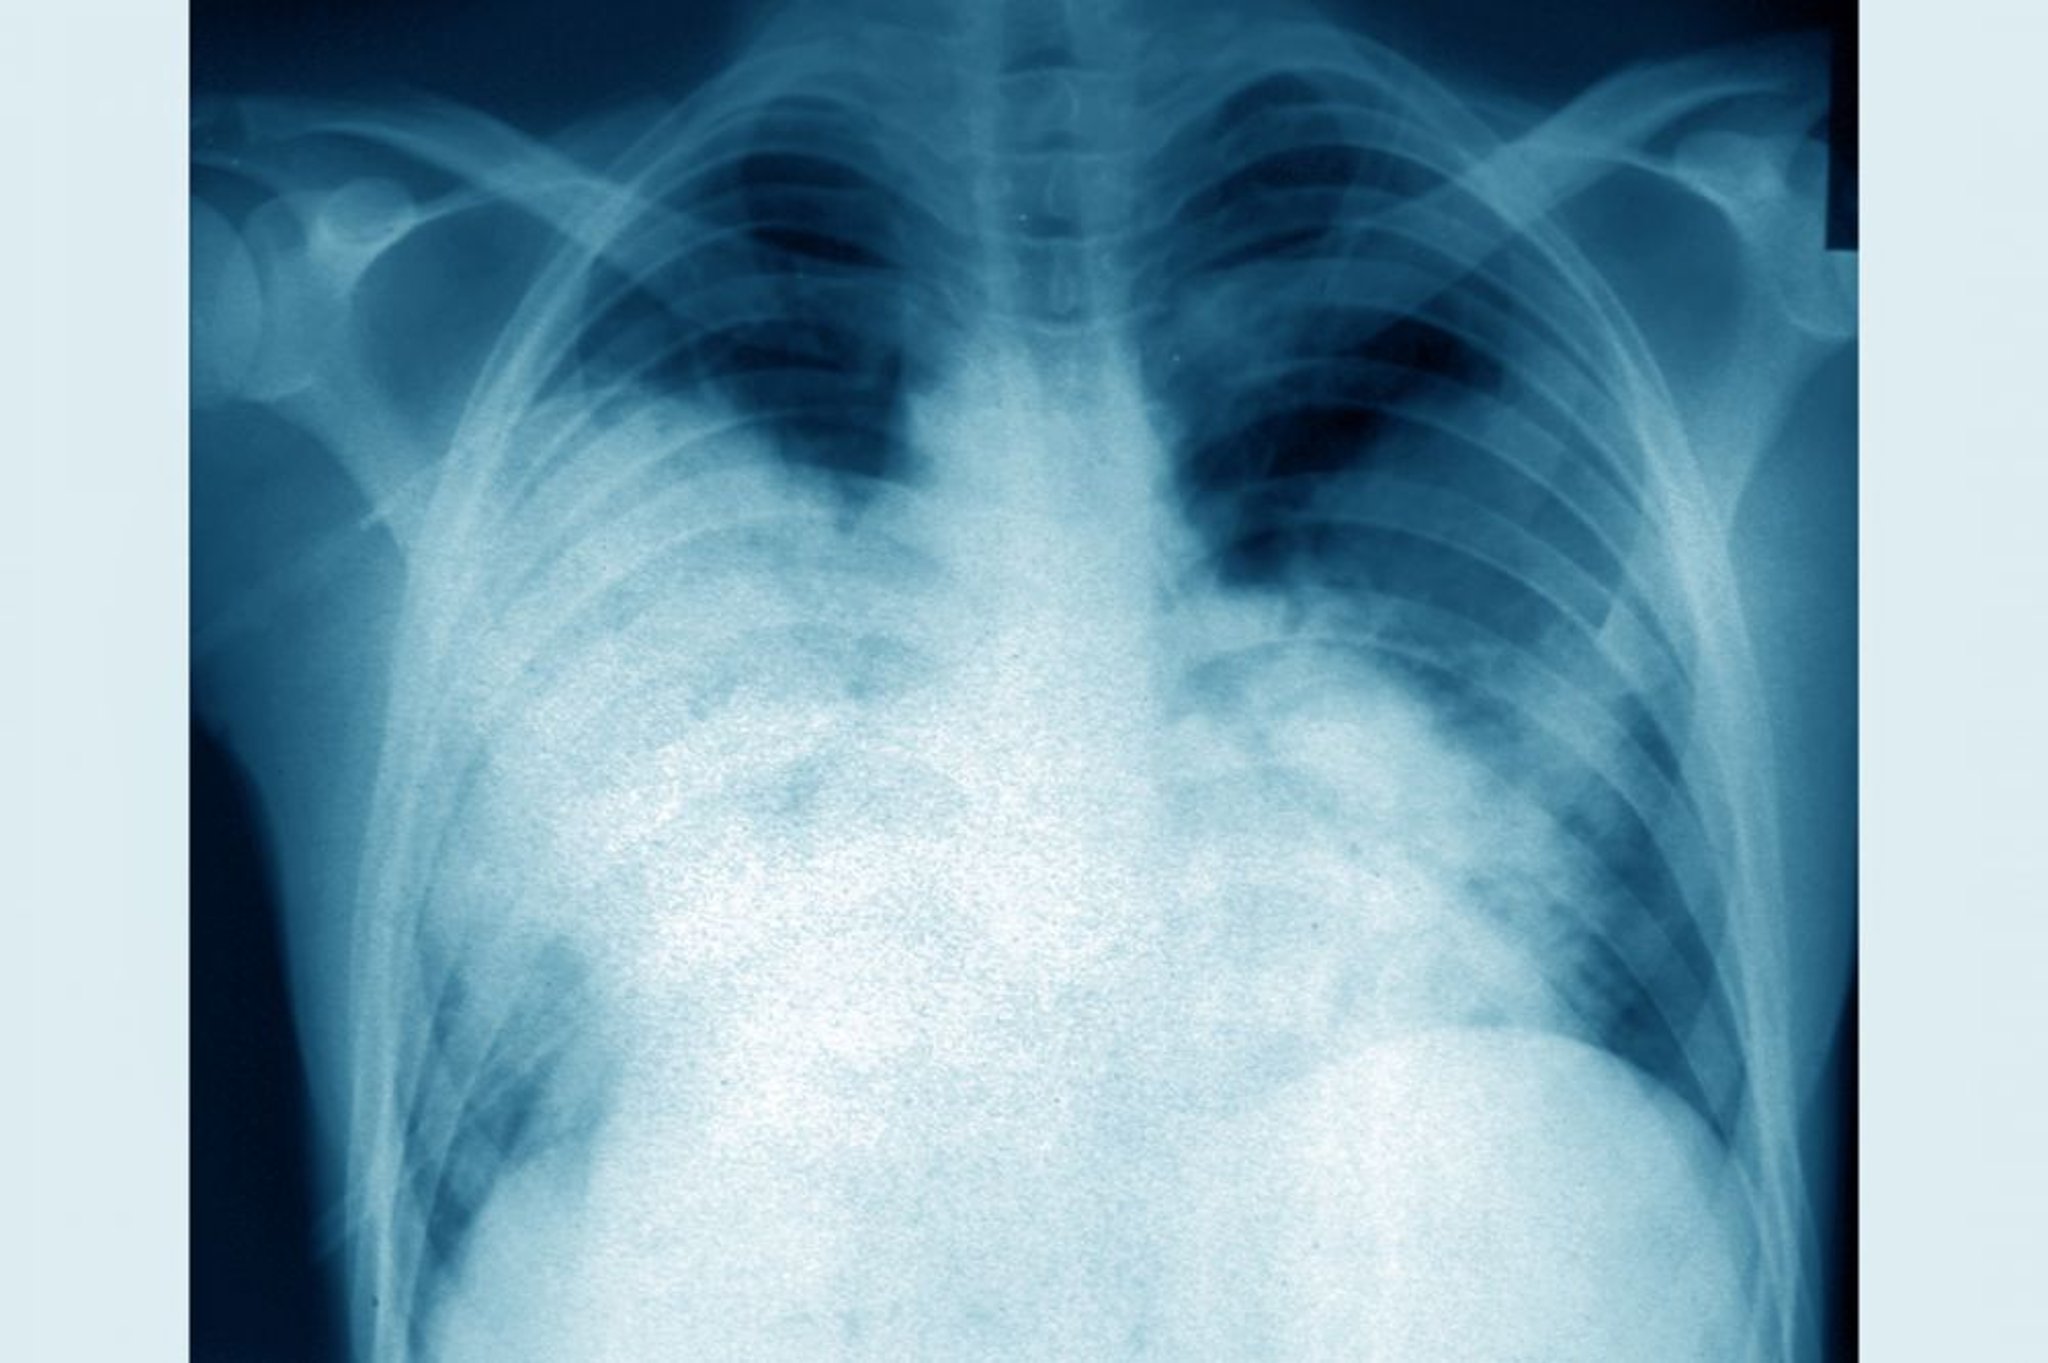

Enfermedad del legionario (radiografía de tórax)

Esta radiografía frontal de tórax muestra una neumonía bilateral aguda (enfermedad del legionario causada por Legionella pneumophila).

CAVALLINI JAMES/BSIP/SCIENCE PHOTO LIBRARY